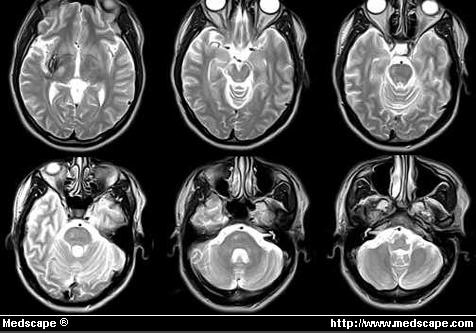

Figure 5. MRI demonstrating brain infarction and degeneration. Reprinted with Permission from Ray Ballinger, MD, PhD. (L’immagine con Risonanza Magnetica evidenzia infarto cerebrale e degenerazione)

La MRI (Risonanza magnetica nucleare) è uno strumento di valido aiuto per investigare sugli effetti sul sistema nervoso centrale nei subacquei.

Con tale tecnica, dei segnali ad alta intensità, visibili come macchie bianche, indicano danni tissutali, e sono stati registrati nei subacquei. Si pensa che siano un indicatore molto significativo per danni al sistema nervoso centrale. La MRI è stata usata per la prima volta dai Norvegesi (Todnem e collaboratori) ( 39) per lo studio della PDD; essi riscontrarono che fino al 33% di tutti i sub avevano tali variazioni di luminosità nei segnali durante l’esame. Studi analoghi di Brubakk ( 40) e Rinck e collaboratori ( 41) hanno confermato tali risultati.